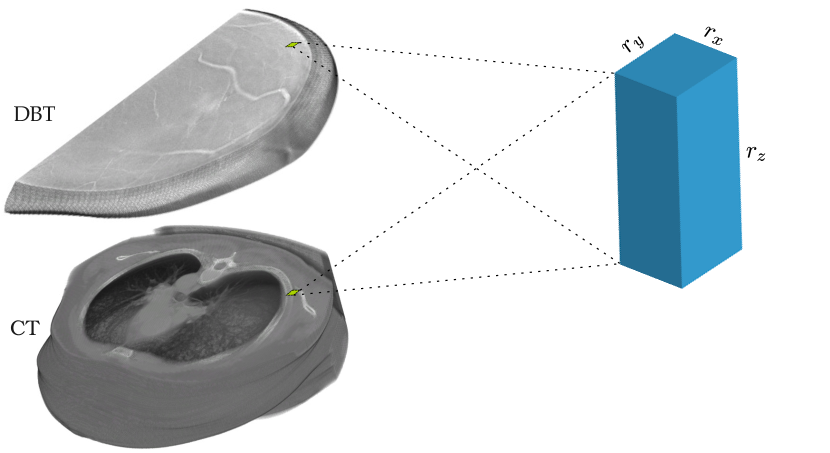

Refer to caption

Figure 1: The example anisotropic volumes of DBT and CT are shown in the left column. Such volumes contain voxels with much higher within-slice resolution rx×rysubscript𝑟𝑥subscript𝑟𝑦r_{x}\times r_{y} than the between-slice resolution rzsubscript𝑟𝑧r_{z}.

Due to the special imaging settings, many imaging modalities come with anisotropic voxels, meaning not all the three dimensions have equal resolutions. For examples, in the 3D volumes of Digital Breast Tomosynthesis (DBT), and sometimes Computed Tomography (CT), the image resolution in xy𝑥𝑦xy plane/slice (or within-slice resolution) is more than ten times higher than that of the z𝑧z resolution (or between-slice resolution). Thus, the xy𝑥𝑦xy slices preserve much more information than the z𝑧z dimension. In DBT images, only the spatial information within the xy𝑥𝑦xy plane can be guaranteed. However, the 3D context between xy𝑥𝑦xy slices, even with slight misalignment, still carries meaningful information for analysis.